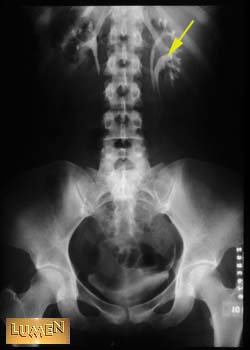

Question: Identify.

Major calyx of kidney.